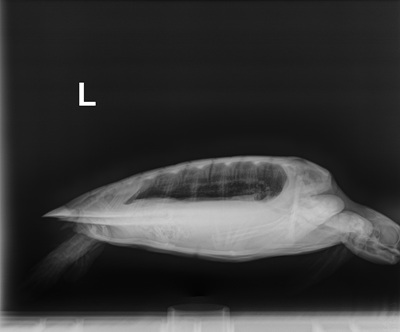

2.7 Atlantic Green Sea Turtle

Patient Injuries

Plastron: Minor abrasion, External Wounds: Minor abrasions to all four flippers.

In House Bloods:PCV: 30 %, TS: 4 , Glucose:127, meds administered: Standard protocol (Ceftaz (antibiotic), VitB (appetite stimulant) & Normosol (fluids for hydration)